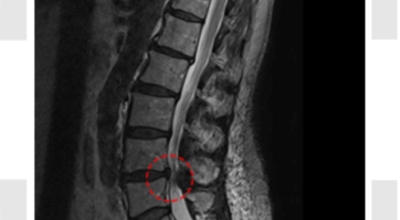

요추관 협착증은 척추 내 신경이 지나가는 통로가 좁아지는 현상으로 기인해서 신경이 눌리면서 이에 따른 여러가지 증상을 유발하는 질환을 의미해요.

허리 협착증은 척추관이 좁아지게 되면서 신경을 압박하게 되어 허리통증과 또한 다리에도 여러가지 증상을 일으키게 되는데, 발생 원인은 주로 노화로 인한 퇴행성 변화가 많았지만 요즈음는 옳지 않은 자세로 오랫동안 앉아있는 사람들이 많아지면서 생기는 경우도 많아졌으며, 선천적인 요인으로 나타나는 경우도 있답니다.